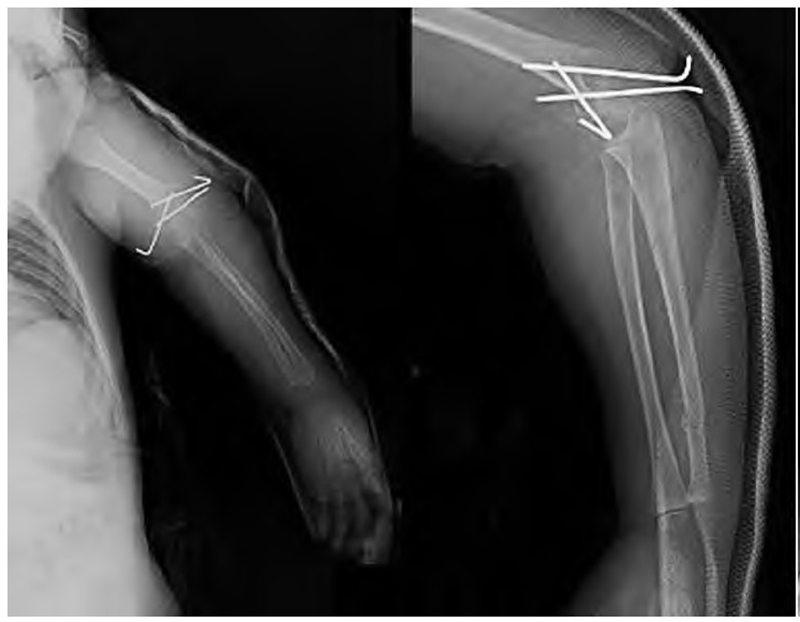

辅助检查:DR 片、CT 扫描及重建示左肱骨髁上骨折,左孟氏骨折,左尺桡骨远端骨折,左肘关节异物(图1)。

图1 术前 DR、CT平扫及重建示左侧肱骨髁上骨折,左孟氏骨折,左尺桡骨远端骨折,左肘关节异物